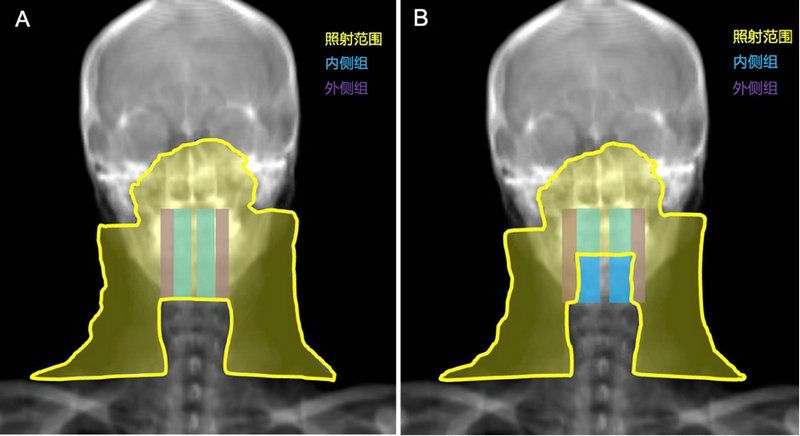

±ÇÑʰ©Ô¤·ÀÕÕÉä¹æÄ£Ê¾Òâͼ

A±ÈÕÕ×飺£ºÄÚ¡¢¡¢¡¢Íâ²à×éÑʺóÁÜͶºÏÇø¾ù½ÓÊÜÔ¤·ÀÕÕÉ䣨×ó£©

BÊÔÑé×飺£ºÄÚ²à×éÑʺóÁÜͶºÏÇø¿íÃâÔ¤·ÀÕÕÉ䣨ÓÒ£©